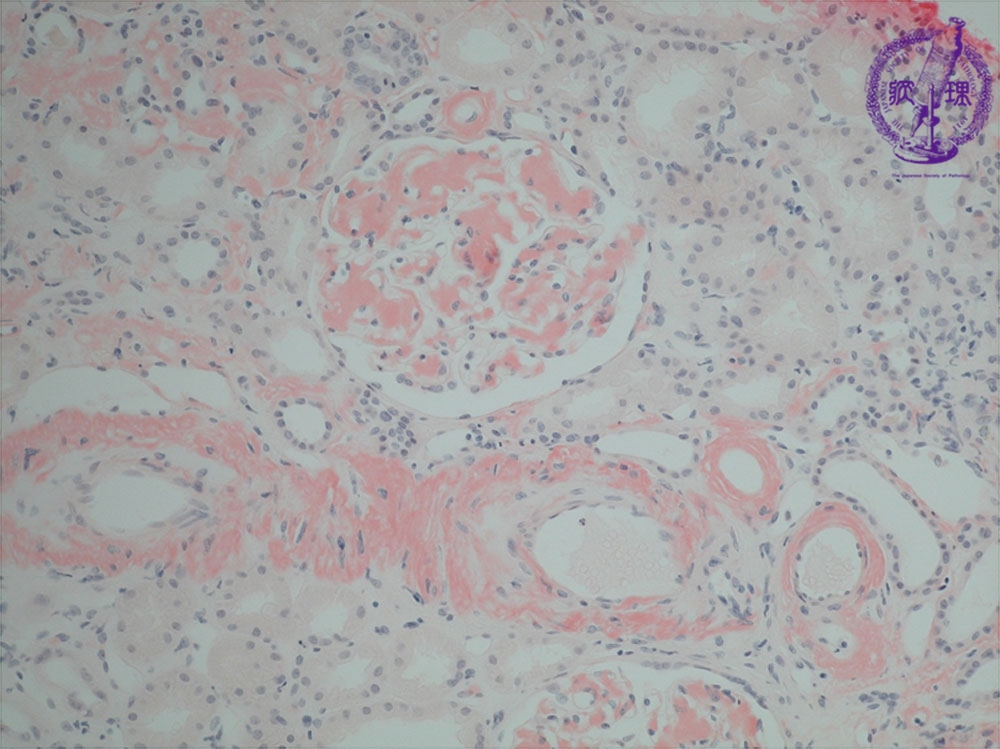

- ★(15)Renal amyloidosis

Microscopic findings ( Congo red, middle power view): Amyloid is (yellow dotted lines) stained orange color with Congo red stain.